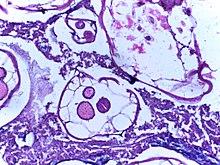

Ascaris infection: Antimesenteric splitting of the outer layers of the bowel wall due to a large amount of ascaris (South Africa)

In extreme cases of intestinal infestation, the mass and volume of the worms may cause the outer layers of the intestinal wall, such as the muscular layer, to tear. This may lead to peritonitis, volvulus, and gangrene of the intestine.[8]